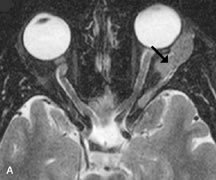

Breast carcinoma metastatic to the orbit has been demonstrated to be hypointense to the surrounding orbital fat on T1-weighted studies and hyperintense on T2-weighted images and has an affinity to the extraocular muscles (Fig. 20).50,64 The MRI characteristics of prostate carcinoma metastatic to the orbit have been described as involving the greater and lesser wing of the sphenoid, orbital roof, and optic canal. Diffuse bone hypertrophy with isointense or slightly hyperintense tissue on T1-weighted images represents the osteoblastic carcinomatous bone infiltration. Contrast enhancement is variable on T1-weighted and fat-suppressed images.65

Fig. 20. A. T1-weighted MR scan demonstrates nodular enlargement of both medial rectus muscles (arrows). B. T1-weighted fat-suppressed contrast-enhanced scan confirms the presence of small metnstatic deposits within the muscles (open arrows).